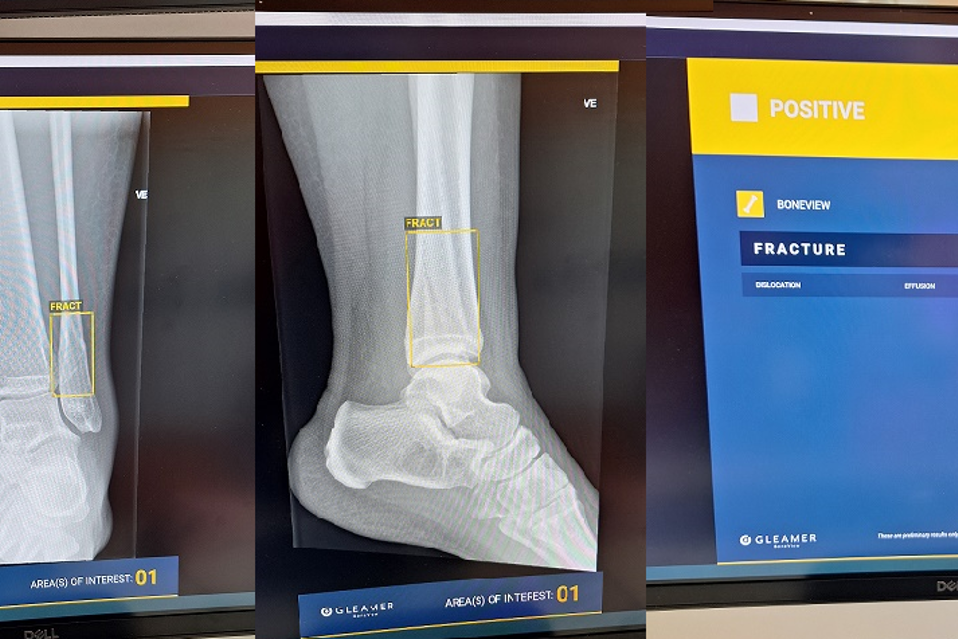

KI programmet skal brukes på akutte skader slik som armbrudd, luksasjoner og andre små skader. Når røntgen er tatt, blir de avidentifiserte bildene automatisk sendt til en skyløsning for tolkning av KI. Deretter blir tolkningen presentert i OUS radiologiprogram Sectra. Så kan at legene raskt vurdere bildene og videre behandling, inkludert om behov for videre bildediagnostikk.

Programmet (som er et av flere KI verktøy på markedet) er trent til å identifisere brudd i arm og ben, samt bekken og ryggrad. Det kan også angi der det er i tvil, samt markere der det tolker at det foreligger en luksasjon (at et ben eller en arm er ute av ledd) og/eller væske i ledd. Verktøyet som heter Bone View (BV) er testet ut og i drift ved bl.a. legevakter i Vestre Viken.